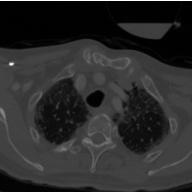

These typical loss functions define the loss of each pixel only on its true and predicted values, but not considering those of other pixels, and aggregate them by weighted averaging or summing without considering the spatial relations between the predictions. Since this type of definition is of local nature, these loss functions may not sufficiently impose a network to learn the shape of an object or the geometry between multiple objects, especially when the amount of training data is small. On the other hand, the ability of the network to learn the shape may be important for better segmenting the objects in medical images since these objects typically have an expected shape or a geometry due to their intrinsic characteristics. One example is the formation of the aortic arch and great vessels in a human body. The aorta and the large arteries and veins (also known as great vessels) are not randomly distributed over the human body. Instead, they are found in a particular geometry due to the human anatomy (Figure 1). Besides, they mostly seem as round objects on a 2D axial image since blood vessels are tubular in 3D. This anatomic information is indeed utilized by human annotators to locate these vessels and delineate their boundaries.

The proposed topology-aware loss function was tested on a dataset that contains CT scans of 24 subjects with prediagnosis of pulmonary embolism. The CT scans were acquired using a 128 slice Philips Ingenuity CT scanner with 1.5 mm slice thickness. A 60 ml of non-ionic contrast material (iohexol; generic name Opaxol) was introduced with a 100 ml saline chaser at 5 ml/s. The data collection was conducted in accordance with the tenets of the Declaration of Helsinki and was approved by Koc University Institutional Review Board (Protocol number: 2022.161.IRB1.064). We randomly split the 24 subjects into the training and test sets. The training set contains 2896 images of 16 subjects; 2234 images of 12 subjects were used to learn the network weights by backpropagation and 662 images of 4 subjects were used as validation images for early stopping. The test set comprises 1431 images of 8 subjects; note that the images of none of these subjects were used neither in the training nor for early stopping.